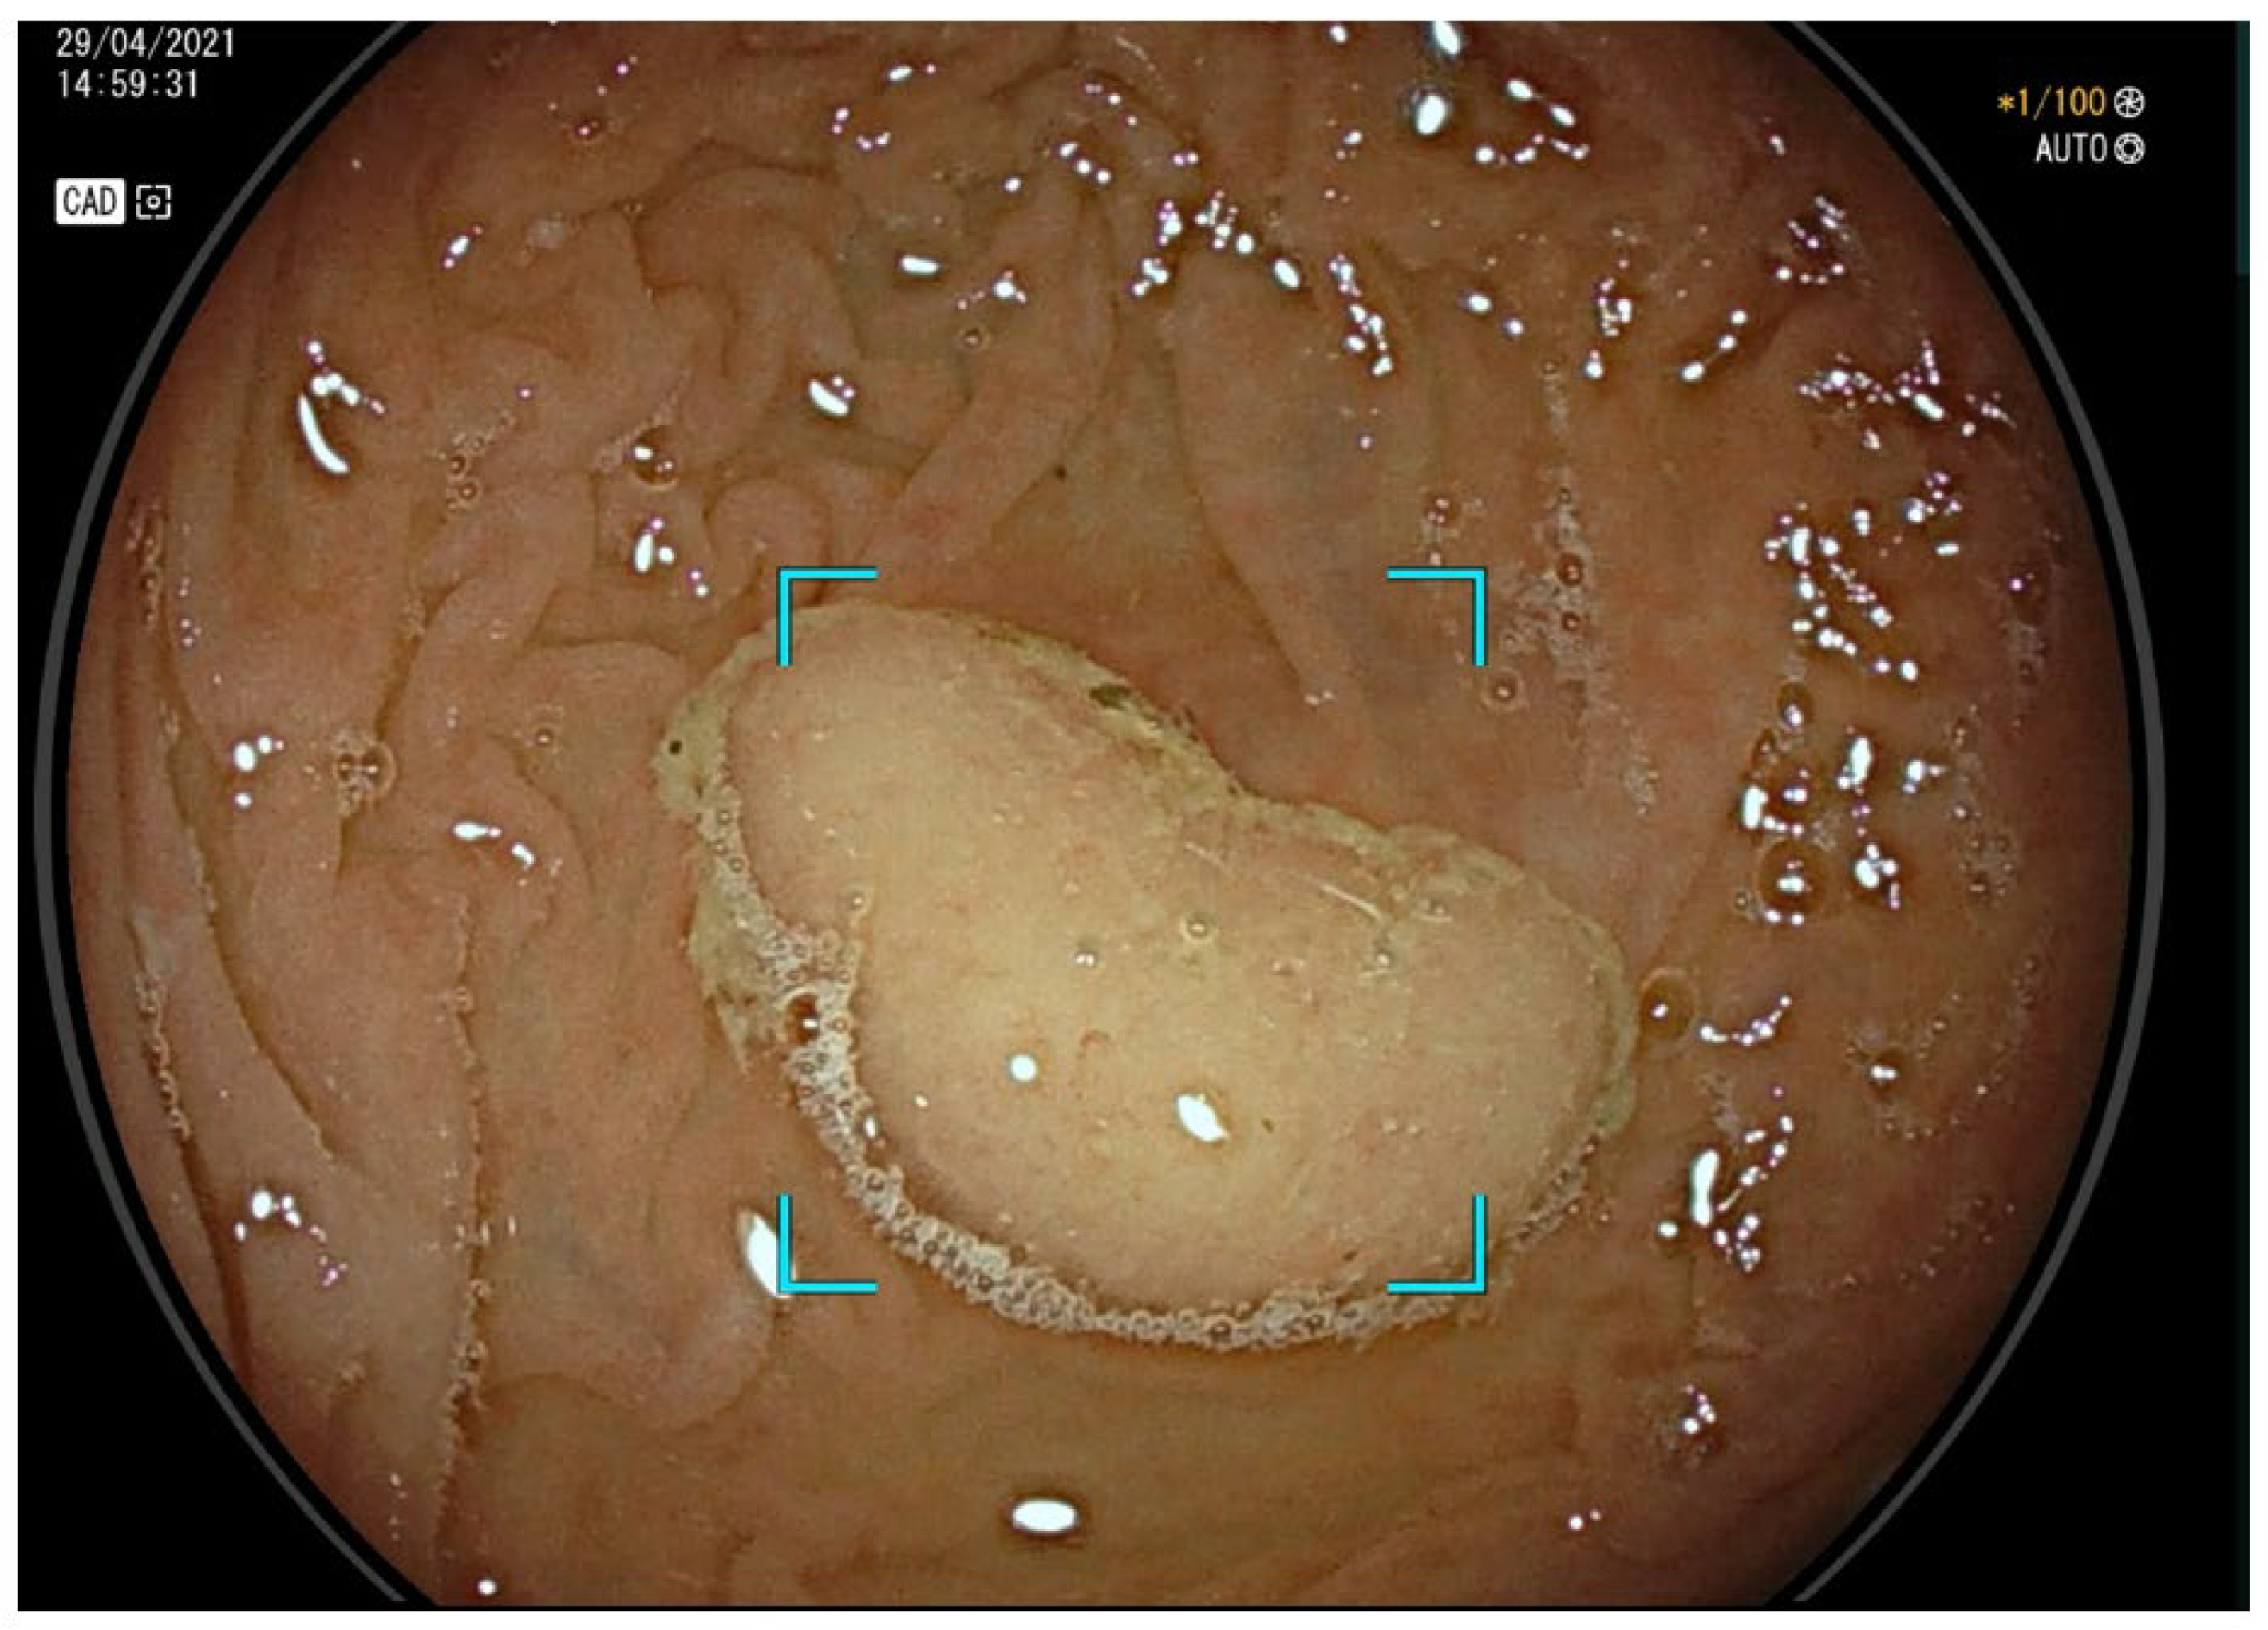

2. CADe and Adenoma Detection

4. CADe and Serrated Lesions